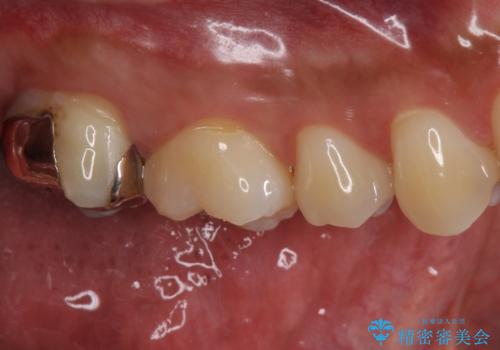

銀歯をなくしたい ジルコニアクラウンでの修復

- 銀歯を白くしたいとのことで来院されました。

歯を覆っている銀の詰め物の面積が広く、セラミックで同じ形態にすると強度に不安が残るため被せ物での修復処置を行っていきます。